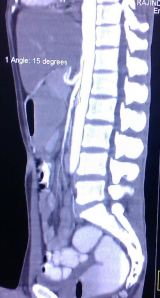

The angle between the aorta and SMA was 15 degrees on CT angiography.